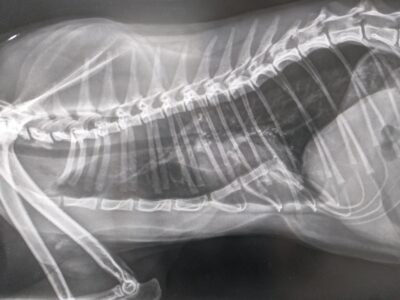

gastric foreign body in lateral

gastric foreign body in lateral -

gastric foreign body in DV

gastric foreign body in DV -